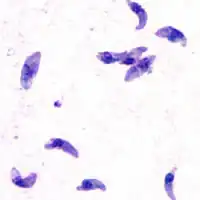

| Tacozoítos de T. gondii | |